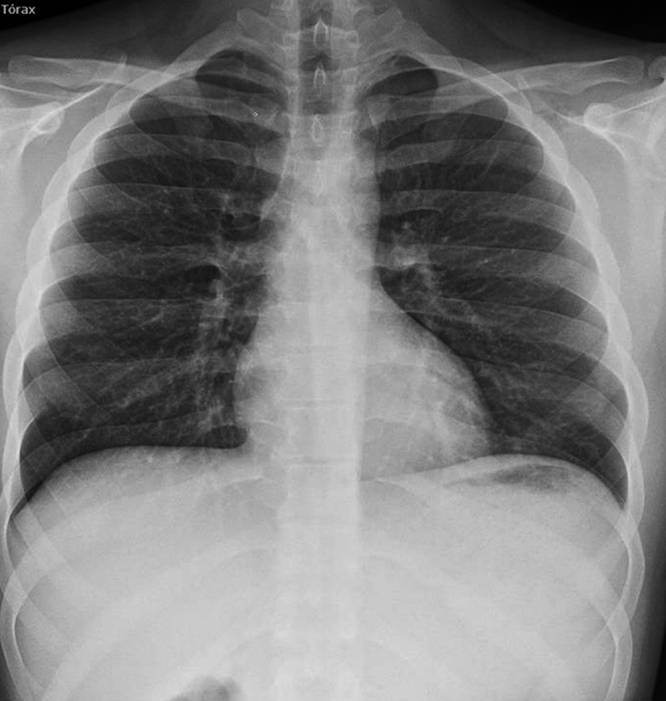

He was hospitalised under observation in A&E, with treatment consisting of oxygen therapy, analgesics and X-ray checks, and was discharged after 24 hours. A subsequent check was carried out by the respiratory medicine section and the family physician, with an X-ray check after 72 hours (Figure 3).

Figura 3. Pneumomediastinum resolved in posteroanterior chest X-ray.